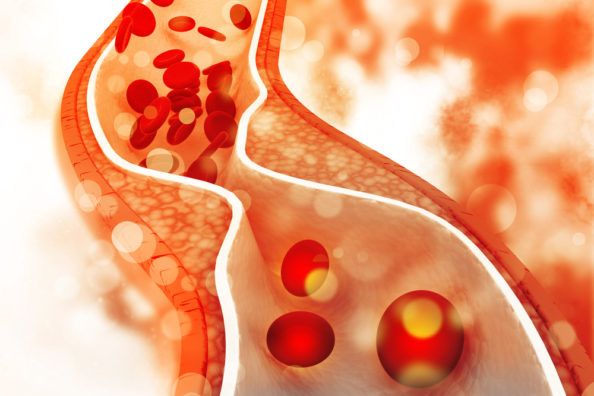

Narrow artery

Two Proteins Allow LDL Cholesterol into Our Cells

Researchers have found out how LDL cholesterol is able to enter our cells with the help of two proteins that form a doorway into the cell. The findings have ramifications for treating heart disease, which is currently the world’s greatest killer.

We have all likely heard about good and bad cholesterol, with high-density lipoprotein (HDL) cholesterol being considered good and low-density lipoprotein (LDL) cholesterol being bad. While this popular summary is somewhat simplistic given that some LDL cholesterol is needed for the body to function correctly, it is true that too much LDL in the bloodstream can be a problem.

LDL cholesterol tends to build up in the walls of our arteries, causing a reduction of blood flow, which typically leads to heart disease, the end result of which is a heart attack or stroke.

In a new study, researchers from the University of New South Wales have discovered how LDL enters our cells by identifying two proteins that function like a gateway in the membrane wall to permit access [1]. This pair of membrane proteins also presents a potential target for drugs that can block their activity and help lower LDL cholesterol levels in the bloodstream.